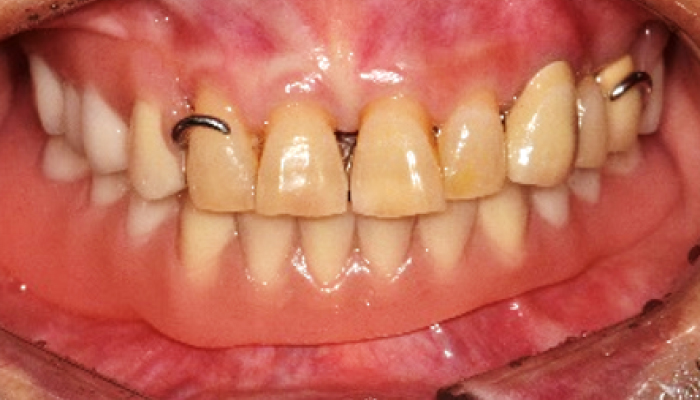

틀니 임플란트 전후 사례

• 식립 전

식립 후